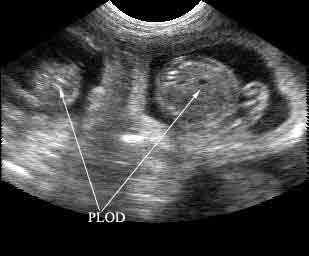

Žal so zunanji znaki pred 35. dnevom brejosti še zelo neizraziti in jih neizkušeni lastnik psice le s težavo odkrije. V takšnem primeru nam bo v veliko pomoč veterinar, ki lahko s pomočjo ultrazvoka ugotovi brejost že nekje med drugim in tretjim tednom, bolj zanesljivo pa okrog 25. dneva. Kljub visoki ceni je s to diagnostično napravo tudi pri nas opremljenih vse več veterinarskih ustanov.

Ultrazvočni posnetek brejosti v starosti približno 6 tednov:

Sicer pa lahko veterinar zarodke (velikosti frnikole), stare 20 do 30 dni, tudi otipa preko trebušne stene, vendar samo pri manjših in bolj suhih psicah. Pri živalih, ki imajo globok trebuh, takšna diagnostika ne pride v poštev, ker majhnih zarodkov ni mogoče zaznati. Kasneje, torej nekako po prvem mesecu brejosti, postanejo zarodki zaradi nabiranja tekočine v ovojnicah mehkejši. Takrat jih tudi pri vitkih psicah ne moremo več zaznati s tipanjem preko trebušne stene. Zanesljivo ugotavljanje brejosti je spet mogoče šele nekako po 45. dneh, ko lahko s pomočjo rentgenskih slik zaznamo tudi kosti mladičkov. Ena izmed prednosti rentgenske preiskave je ta, da lahko zarodke tudi preštejemo, kar je z ultrazvokom manj zanesljivo.